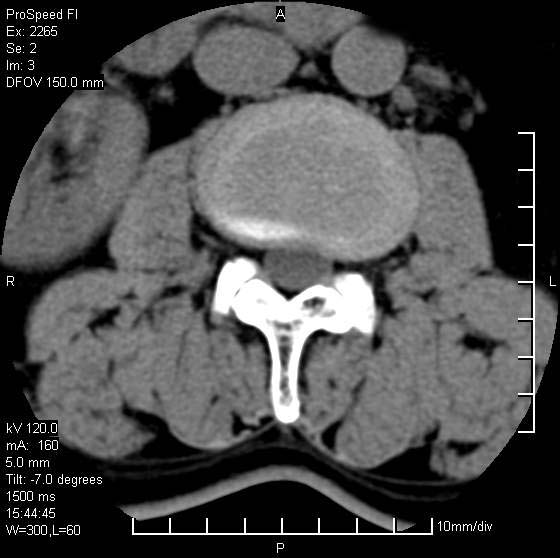

以下是引用qiushi在2007-8-22 17:26:00的发言:[br]没骨窗![br] 1、 l5~s1间盘膨出伴轻度突出(中央型)、变性。[br] 2、l4~5间盘膨出伴突出(右侧远外侧型)。[br] 3、l3~4间盘膨出。[br] 4、腰椎退行性变。[br]

以下是引用随缘的人在2007-8-22 20:56:00的发言:[br]腰椎退行性变:1。l4/5,l5/s1膨出[br] 2。l5/s1间盘退行性变 [br] 3。腰椎骨质增生

以下是引用liaizhi在2007-8-22 22:13:00的发言:[br]1,l4-5锥间盘膨出,2,l5-s1椎间盘膨出并退变(椎间盘呈真空征);3,血管瘤(椎体骨小梁稀疏粗大)?